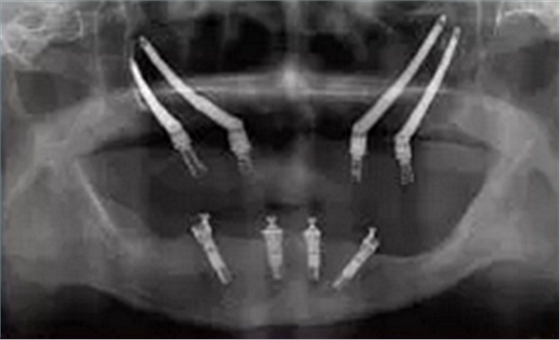

圖 3 雙顴種植體植入術(shù)后全景片

Figure 3 Radiographic of post?surgery of quad zygomatic implants placement

前牙區(qū)剩余骨量嚴(yán)重不足而無法植入常規(guī)種植體的患者, 不符合顴骨種植的經(jīng)典術(shù)式適應(yīng)癥。Bothur[16]等學(xué)者提出單側(cè)顴骨植入多枚種植體的可行性, 并分別于雙側(cè)顴骨各植入2枚和3枚種植體, 繼而提出雙側(cè)顴骨各植入2枚顴骨種植體的改良術(shù)式(zygomatic quad approach)[17, 18, 19, 20], 又稱之為雙顴種植體植入術(shù)(圖3)。該改良術(shù)式較經(jīng)典術(shù)式的適應(yīng)癥更為廣泛, 能獲得更加優(yōu)化的植體受力分布。但研究指出[21], 單側(cè)顴骨植入2枚種植體時(shí), 更容易出現(xiàn)種植體位置過近, 傷及眼球、眶下神經(jīng)血管等重要解剖結(jié)構(gòu), 引起嚴(yán)重的手術(shù)并發(fā)癥。 為了提高顴種植體植入手術(shù)的精準(zhǔn)性和安全性, 目前臨床上有學(xué)者使用計(jì)算機(jī)輔助手術(shù)導(dǎo)航技術(shù)來幫助完成手術(shù)(圖4 ~ 5)。